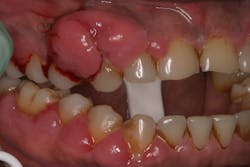

One reason people develop gummy smiles is inflammatory-induced gingival enlargement, typically caused by biofilm (bacteria) and the host response. Gum disease (gingivitis and periodontitis) can result in gum tissue swelling, redness, gum overgrowth, and bleeding (figure 1). In addition to bacterial infiltration of the gums due to poor oral hygiene, orthodontic appliances have been associated with gingival enlargement since braces can act as food traps (figure 2).Further reading: Considerations when using veneers to fabricate a perfect smile